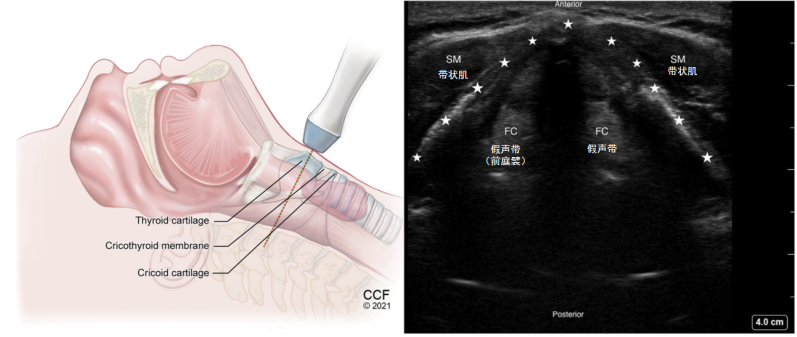

(2)甲状软骨横切面:将探头继续下滑就到了甲状软骨切面,在最上面会看到一个倒“V”形低回声线性结构,即图9中五角星标记处,此处即为甲状软骨。同时还会看到两个对称的回声相对较高的结构,但不是声带,而是位于声带之上的前庭襞。当我们发出类似于嘶吼的声音,假声带会收缩,帮助我们发声。

图片

图9 甲状软骨横切面